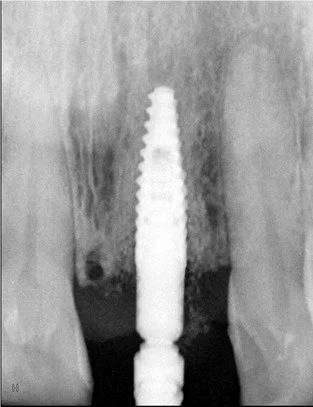

Control radiográfico inmediato del implante